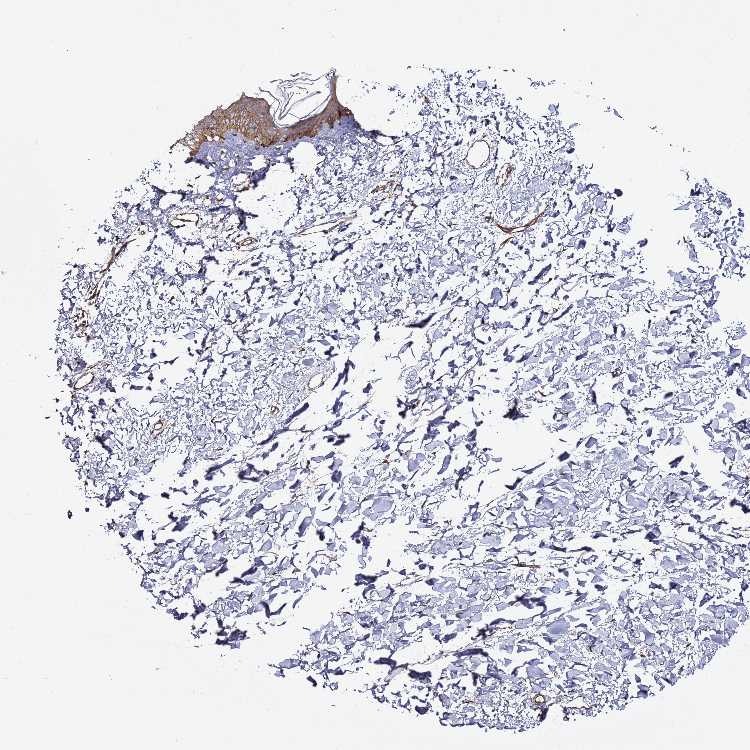

SKIN 1 - Antibody stainingi

Antibody staining in the annotated cell types in the current human tissue is reported as not detected, low, medium, or high, based on conventional immunohistochemistry profiling in selected tissues. This score is based on the combination of the staining intensity and fraction of stained cells.

Each image is clickable and will lead to virtual microscopy that enables deeper exploration of all samples and also displays staining intensity scores, fraction scores and subcellular localization as well as patient and tissue information for each sample.

Antibody HPA043338Antibody CAB033575

Langerhans MediumLow

Fibroblasts HighMedium

Keratinocytes MediumMedium

Melanocytes MediumLow

SKIN 2 - Antibody stainingi

Epidermal cells MediumMedium